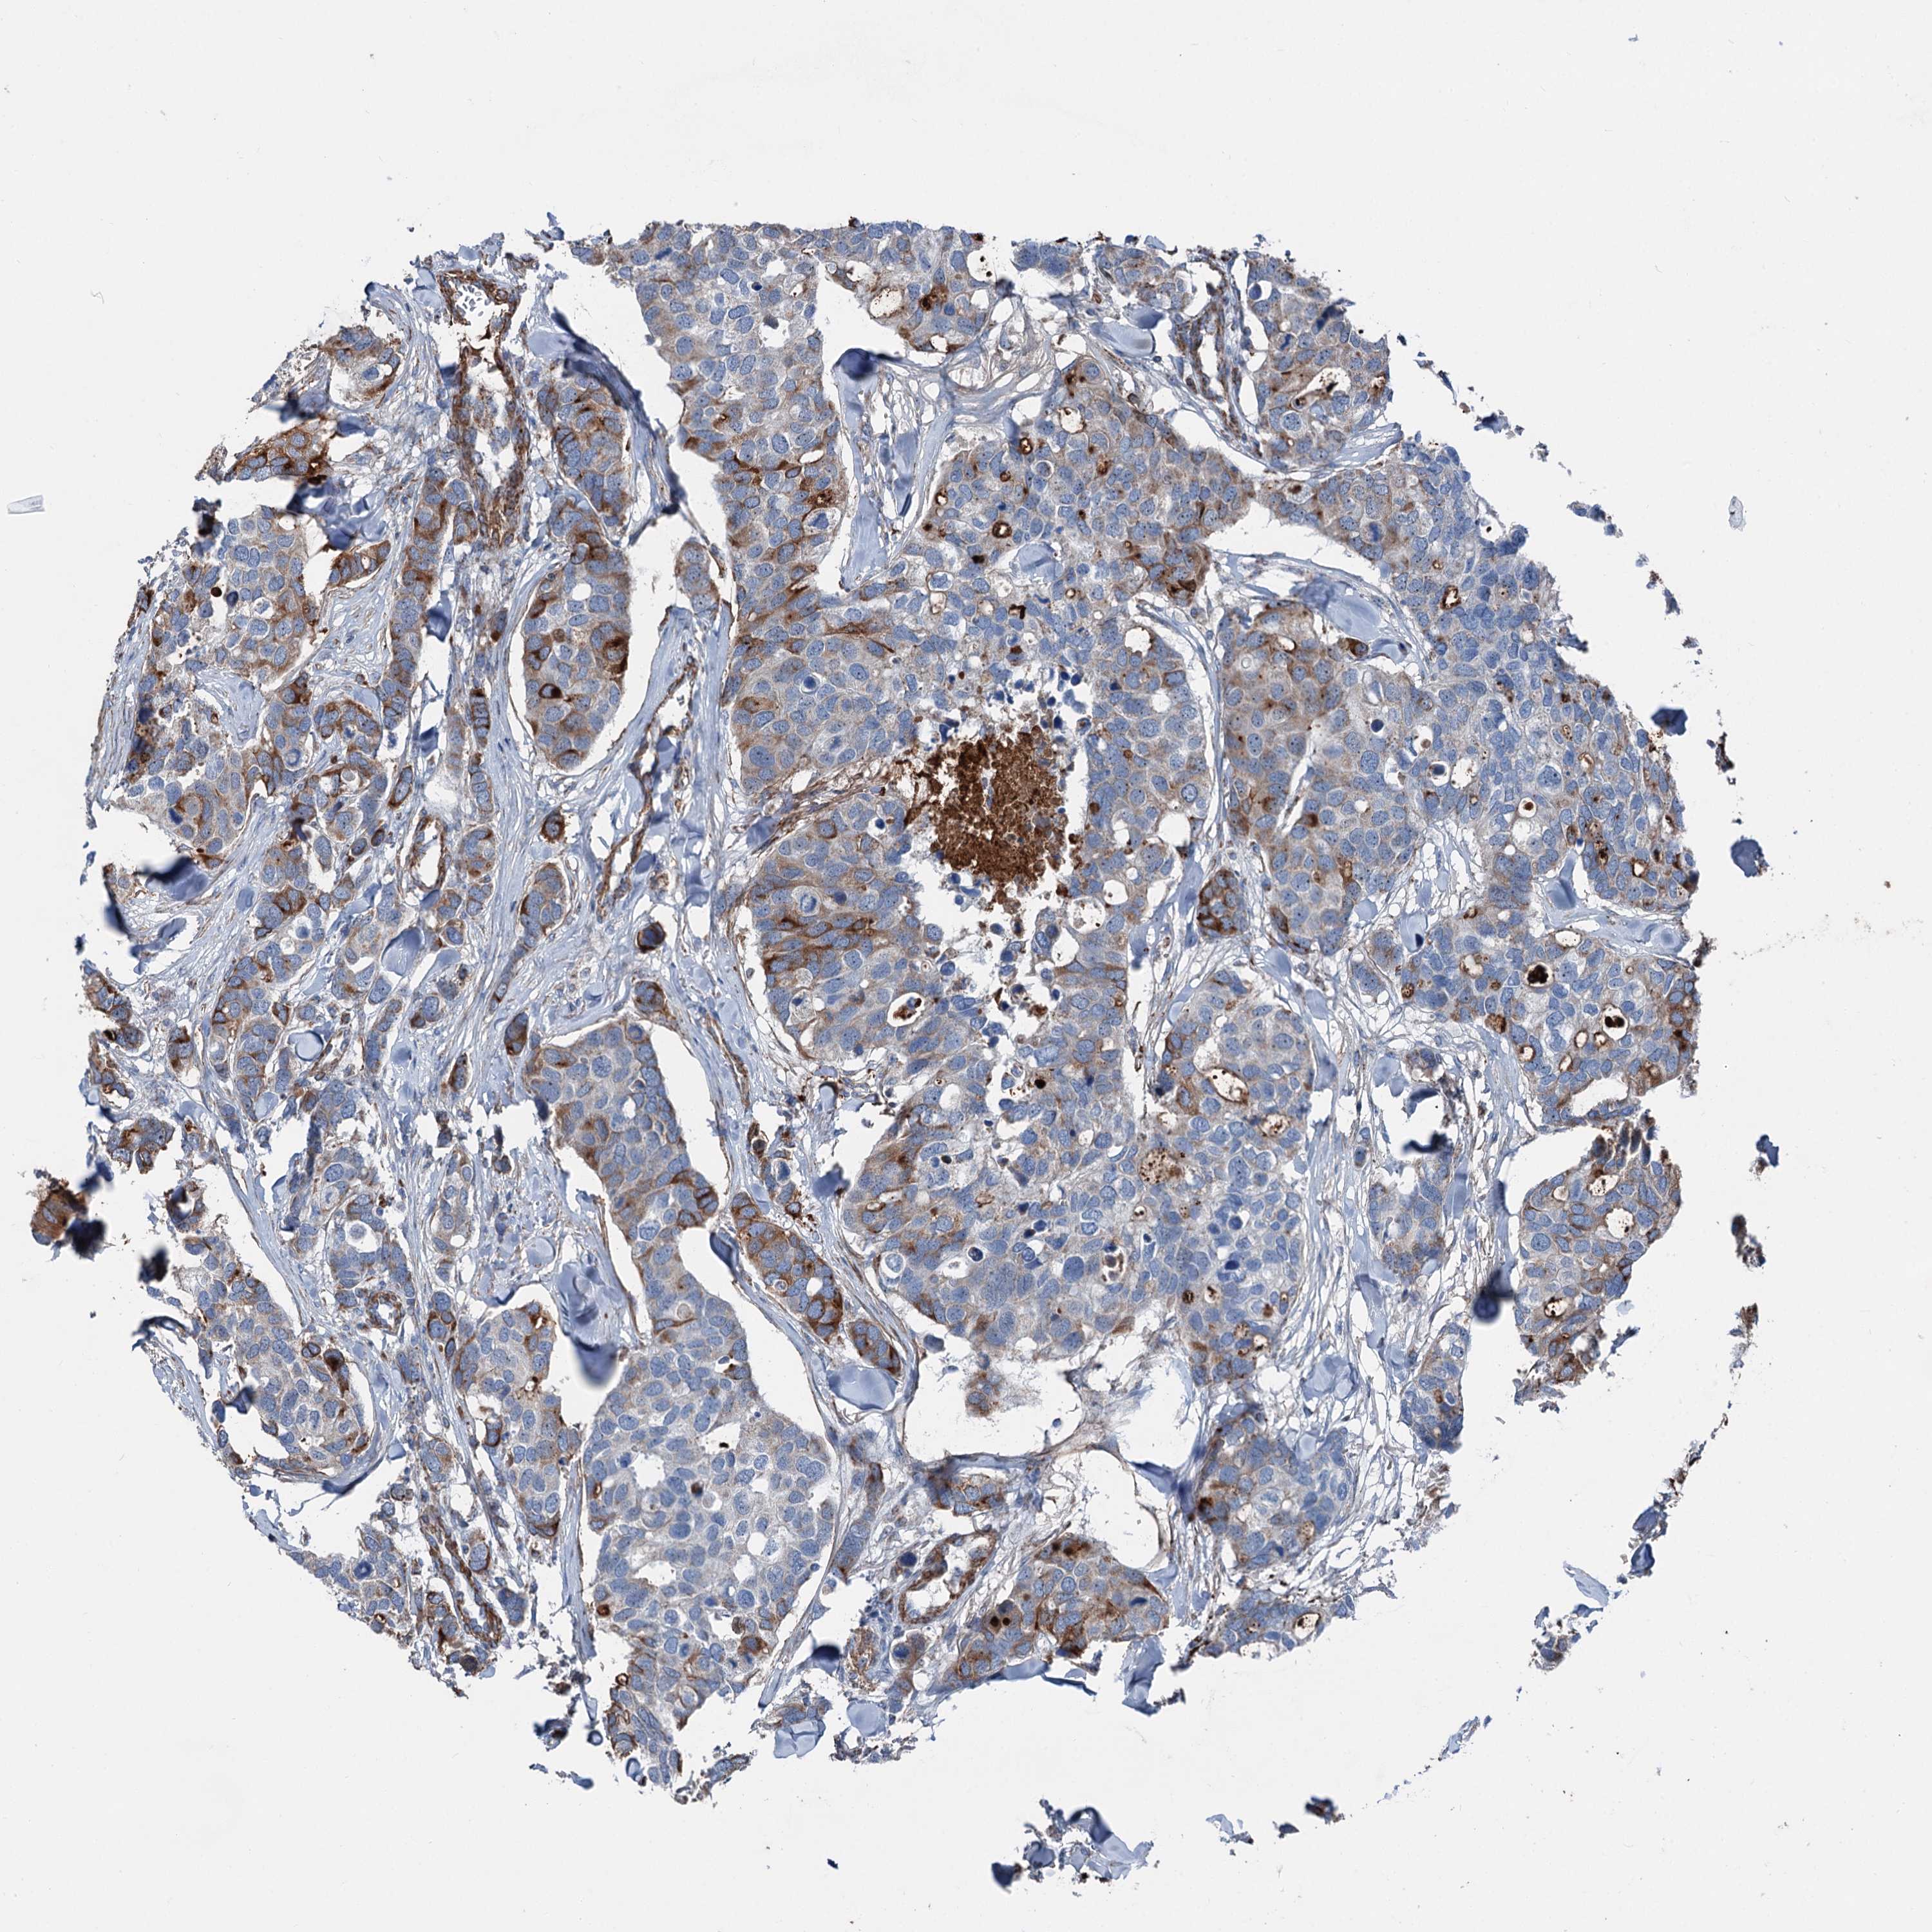

CANCER BREAST CANCER Show tissue menu

BRCA TCGA BRCA VALIDATION PROTEIN EXPRESSION